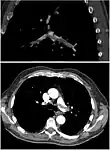

CT pulmonary angiography

CT pulmonary angiography (CTPA) is a pulmonary angiogram obtained using computed tomography (CT) with radiocontrast rather than right heart catheterization. Its advantages are that it is accurate, it is non-invasive, it is more often available, and it may identifying other lung disorders in case there is no pulmonary embolism. The accuracy and non-invasive nature of CTPA also make it advantageous for people who are pregnant.[59]

Assessing the accuracy of CT pulmonary angiography is hindered by the rapid changes in the number of rows of detectors available in multidetector CT (MDCT) machines.[60] According to a cohort study, single-slice spiral CT may help diagnose detection among people with suspected pulmonary embolism.[61] In this study, the sensitivity was 69% and specificity was 84%. In this study which had a prevalence of detection was 32%, the positive predictive value of 67.0% and negative predictive value of 85.2%. However, this study's results may be biased due to possible incorporation bias, since the CT scan was the final diagnostic tool in people with pulmonary embolism. The authors noted that a negative single slice CT scan is insufficient to rule out pulmonary embolism on its own. A separate study with a mixture of 4 slice and 16 slice scanners reported a sensitivity of 83% and a specificity of 96%, which means that it is a good test for ruling out a pulmonary embolism if it is not seen on imaging and that it is very good at confirming a pulmonary embolism is present if it is seen. This study noted that additional testing is necessary when the clinical probability is inconsistent with the imaging results.[62] CTPA is non-inferior to VQ scanning, and identifies more emboli (without necessarily improving the outcome) compared to VQ scanning.[63]